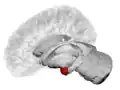

Frontal and side view of amygdala

Left lateral view of the amygdala in an average human brain